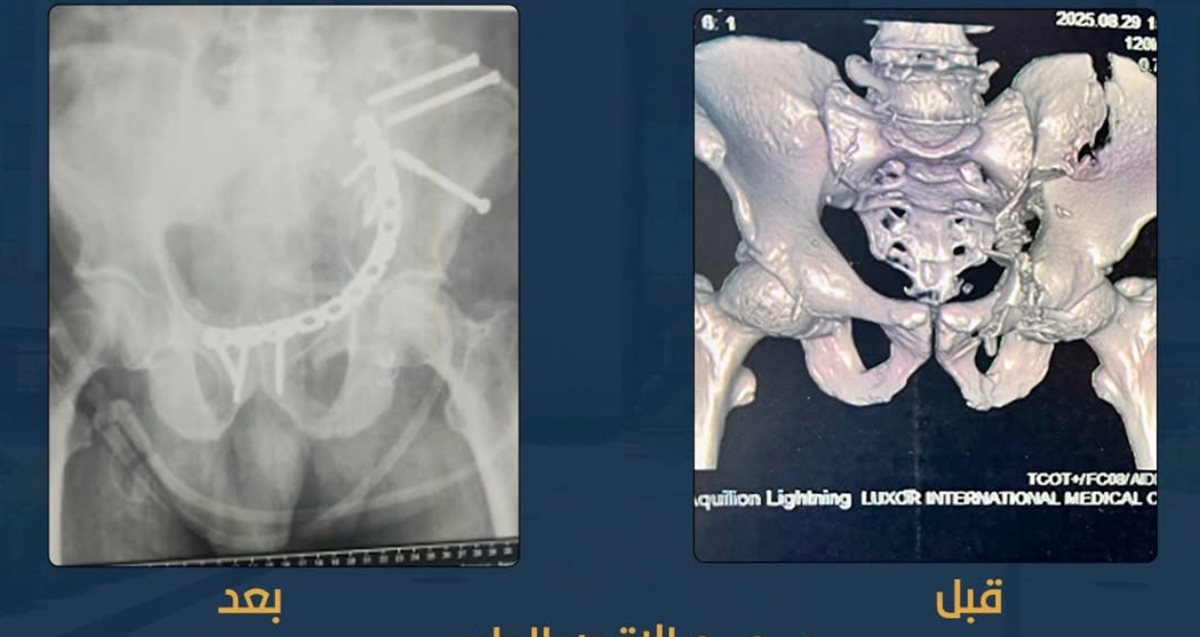

عظامه متفتتة.. نجاح عملية جراحية دقيقة لتثبيت كسور بالحوض لمريض بمجمع الأقصر الطبي الدولي

أعلن مجمع الأقصر الطبي الدولي التابع لهيئة الرعاية الصحية، نجاح عملية جراحية معقدة لتثبيت كسور الحوض لمريض كان يعاني من تفتت كامل في عظام الحوض، حيث أُجريت العملية باستخدام الشرائح والمسامير لتثبيت العظام وإعادتها إلى وضعها الطبيعي.

قاد العملية نخبة من أطباء جراحة العظام والتخدير، مدعومين بفريق تمريض مدرَّب، حيث جرى التدخل الجراحي بدقة عالية مع اتخاذ كافة الإجراءات الطبية اللازمة لضمان استقرار حالة المريض.